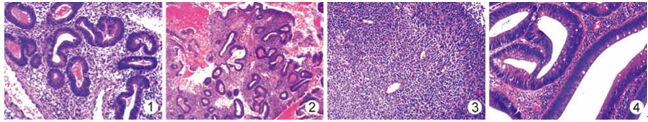

经过格林环保试剂处理的组织切片染色均匀鲜亮,颜色对比度更好、着色更清晰,镜下核浆对比效果好。其中子宫内膜(图1,2)、淋巴组织(图3)、子宫肌瘤和肠组织(图4)等组织脱水彻底,结构鲜明,切片质量高。切片染色的******、染色质量的稳定,有助于病理诊断工作质量的稳定和提高。

图1子宫内膜组织 图2子宫内膜组织 图3淋巴结穿刺活检组织 图4肠活检组织